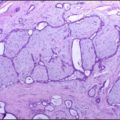

Conn Syndrome (Hyperaldosteronism)

Conn syndrome is a rare disorder known as primary aldosteronism.

Conn syndrome is brought on by an excess of the hormone aldosterone, which regulates the levels of sodium and potassium in the blood.

Adrenal adenomas are the most frequent cause of Conn syndrome, but sporadic adrenal hyperplasia and adrenal hyperplasia are less frequent causes.

Conn syndrome is characterized by high aldosterone and low renin where high blood pressure down regulates renin via negative feedback.